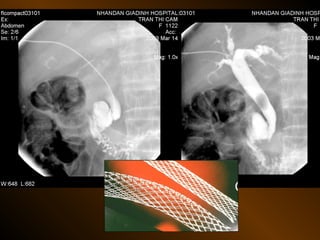

X QUANG CAN THIỆP

Dẫn lưu áp xe bụng

Thủ thuật nghẽn mạch cầm máu

Dẫn lưu đường mật